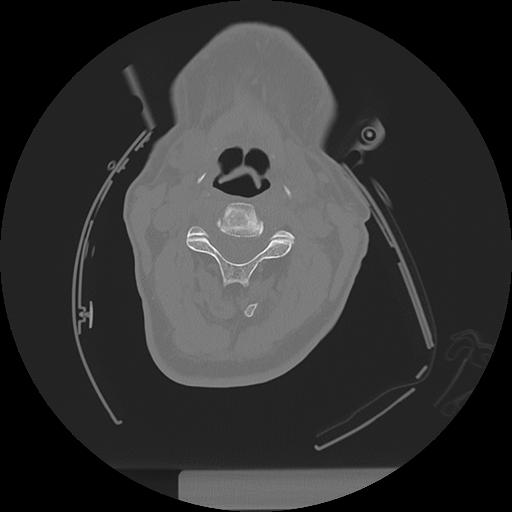

11 HUESO,,Axial,2.0,HUESO,,